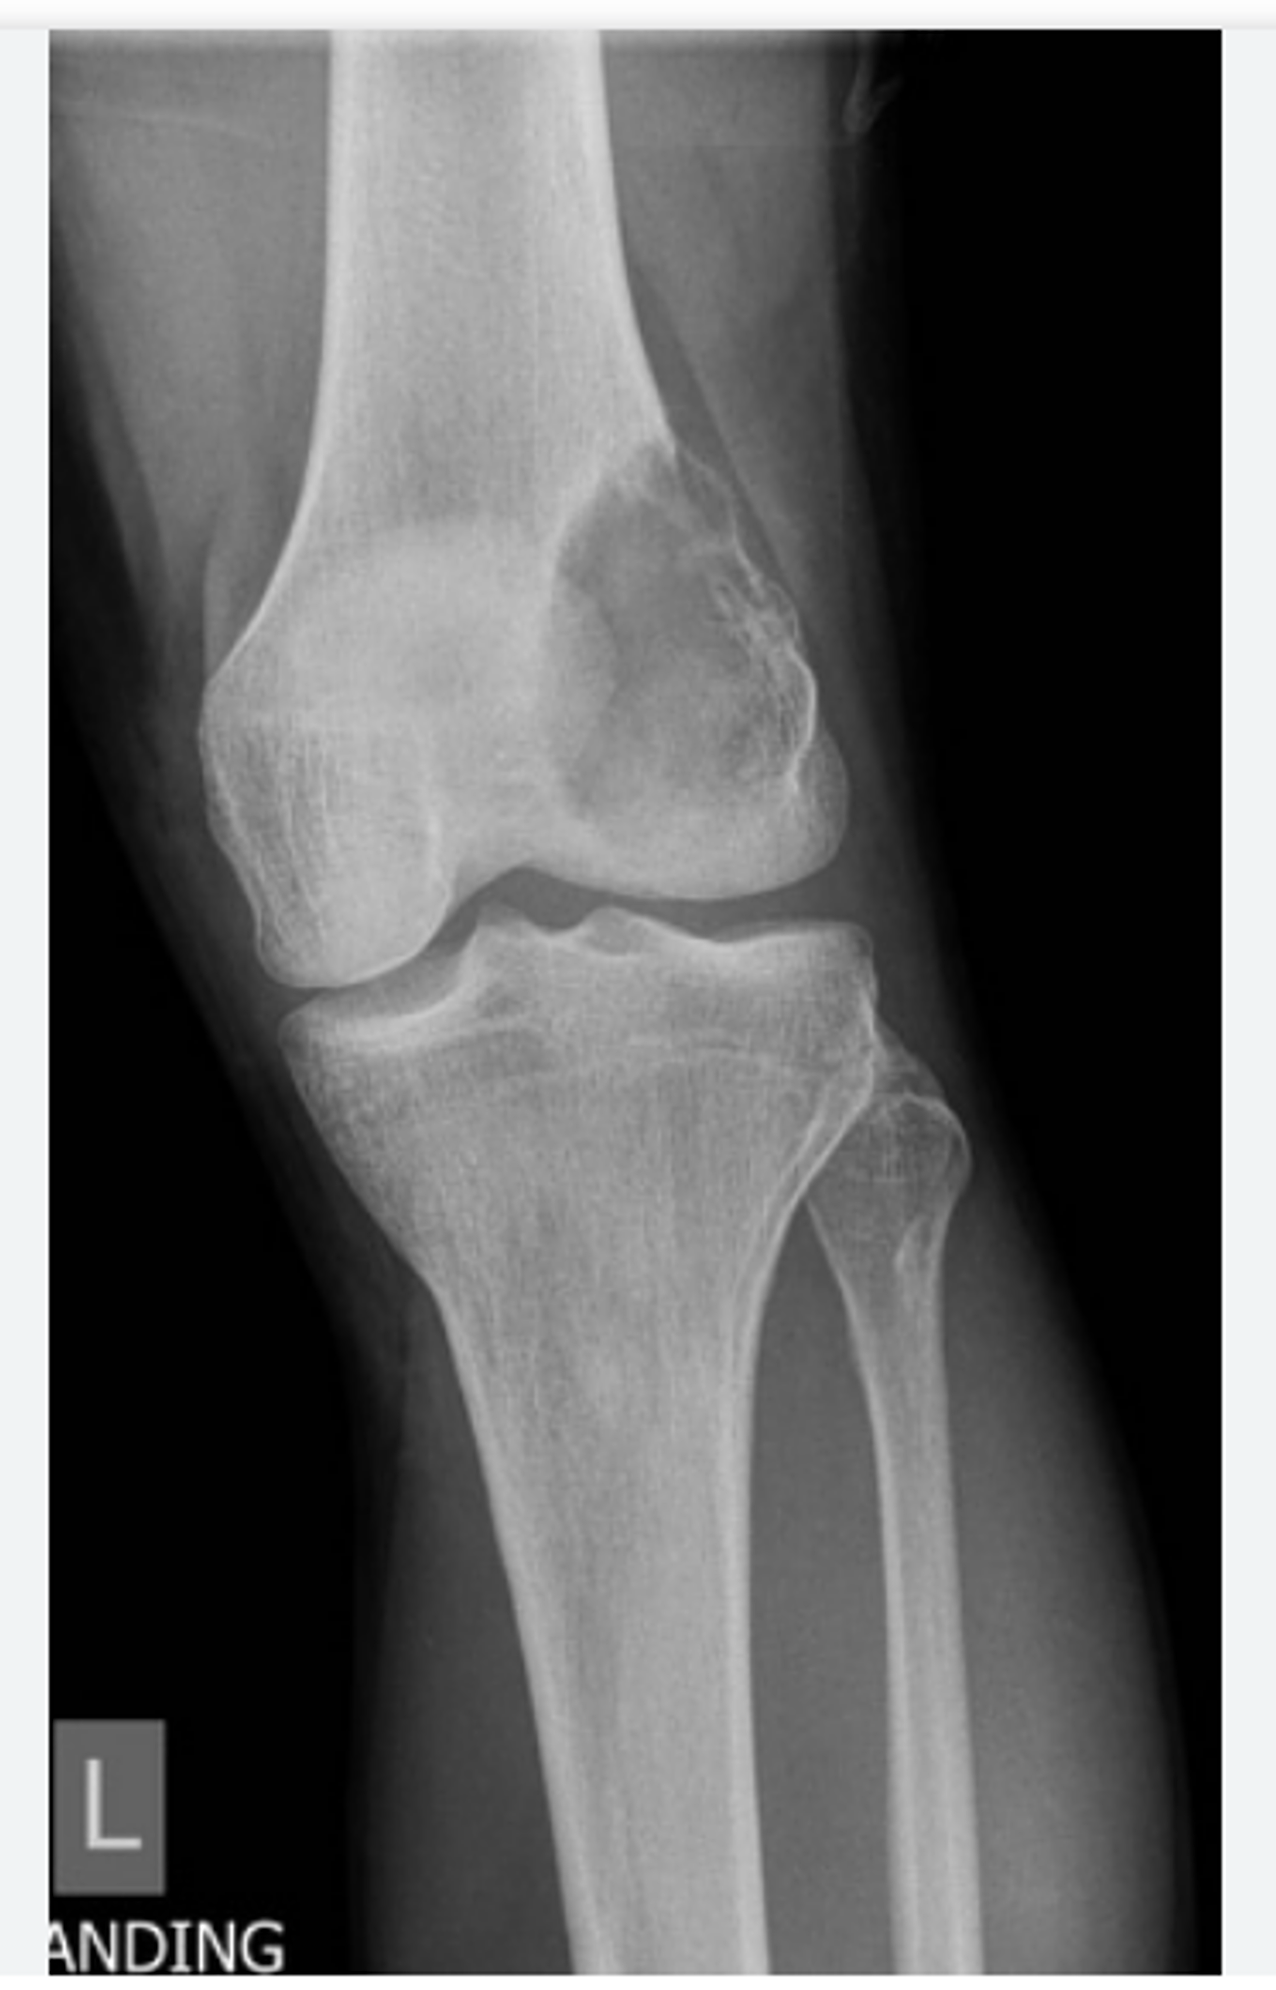

What is an osteosarcoma?

• Paget disease or radiation can predispose

• the tumour is highly malignant and secretes osteoid

• local spread occurs quickly, destroying the cortex, but it may also metastasise

• (most common in knee, proximal humerus, femur)

Osteosarcoma (symptoms, x-ray)...

- most common primary bone malignancy, occurs mainly in adolescent males - symptoms: warm, painful swelling, most commonly at knee - x-ray: periosteal reaction with codman's triangle and a sunburst appearance